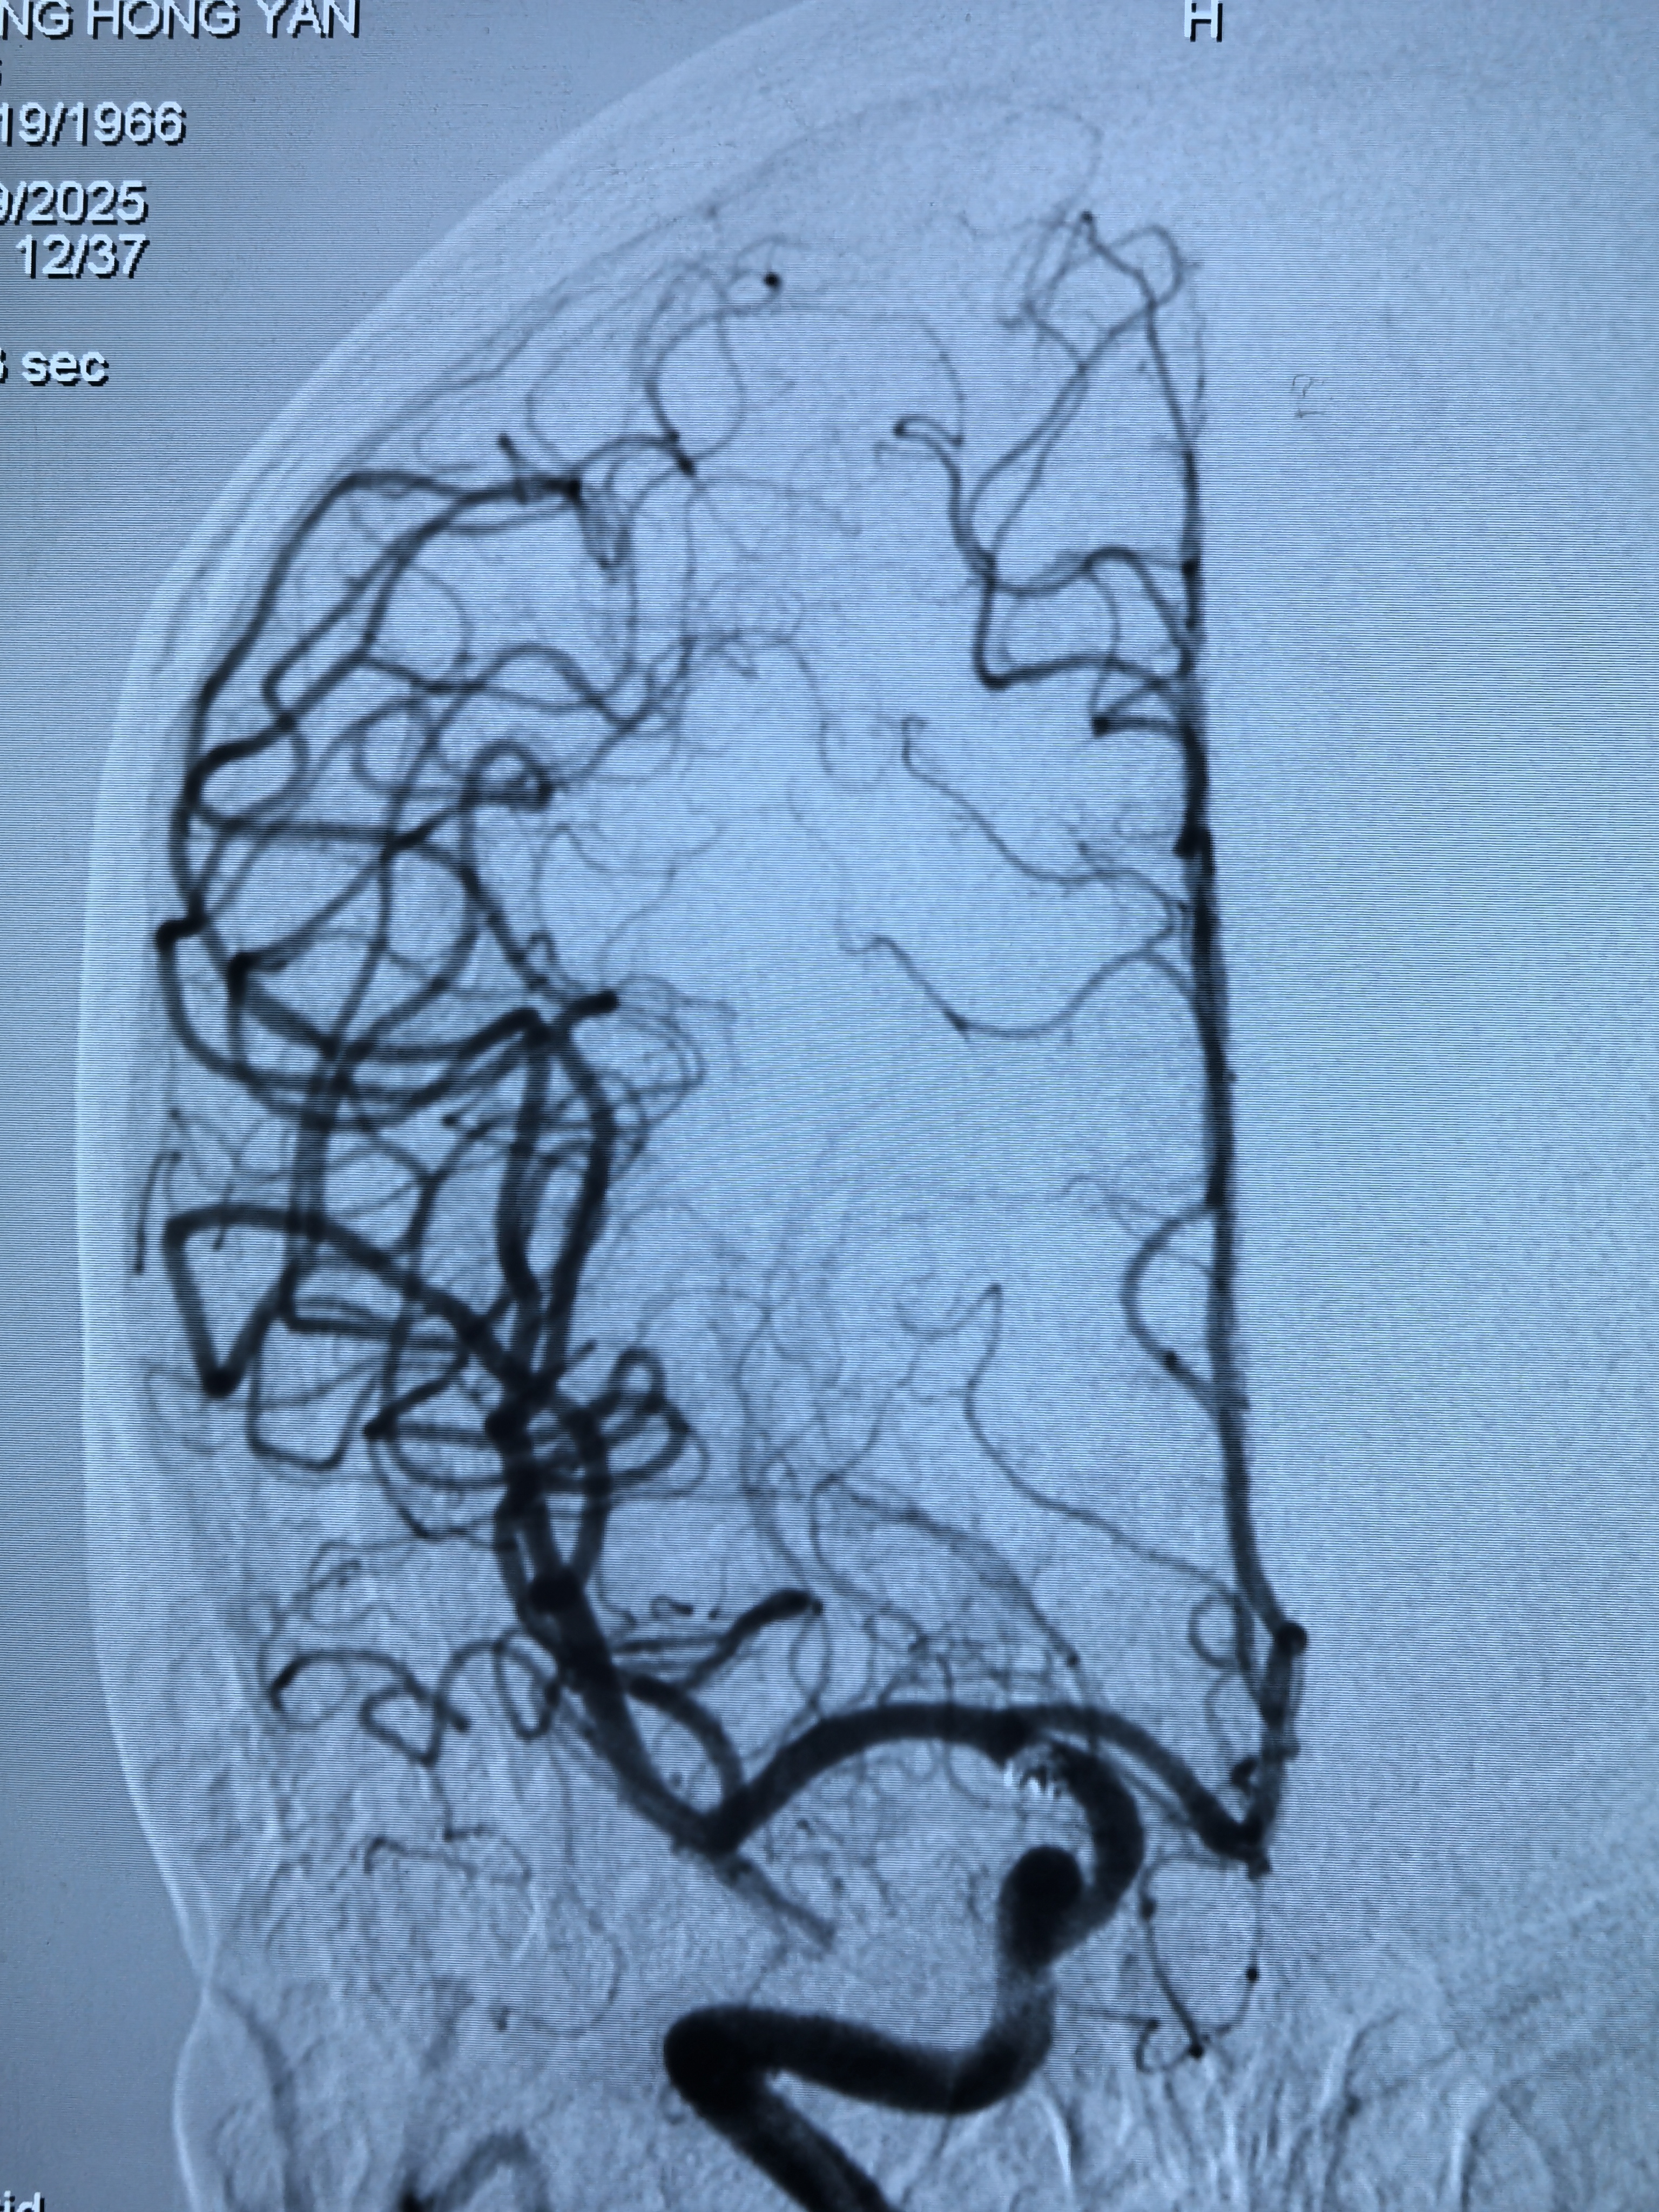

右侧颈内动脉脉前动脉瘤单栓!